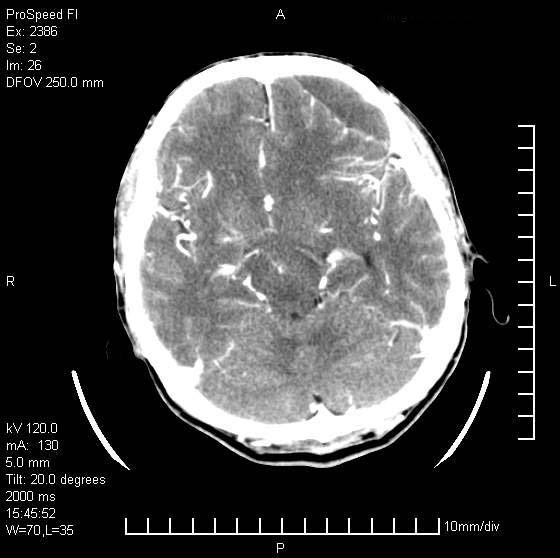

以下是引用天南地北在2007-9-19 18:43:00的发言:[br]典型慢性硬膜外血肿[br][br][本贴已被 天南地北 于 2007-9-19 18:44:11 修改过]

以下是引用曼一拍在2007-9-20 11:06:00的发言:[br]支持慢性硬膜下血肿.[br]慢性硬膜下积液:血肿有包膜,ct值稍高于脑脊液,增强可有染色。不典型者血肿可多呈梭形.是硬脑膜与蛛网膜之间的潜在腔隙内的血肿。[br]鉴别:[br]1\\硬膜外血肿:是颅脑外伤后脑膜或板障内血管破裂,血液在颅骨与硬膜之间积聚所致.通常是脑膜动脉破裂,也可因静脉窦破裂或颅骨的板障静脉出血,发生于外伤的着力部,常与颅骨骨折并存。脑膜动脉出血则急,若是板障静脉出血在则可有慢性。[br]2\\硬膜下积液:(硬膜下水瘤)[br]是由于蛛网膜破裂,脑脊液经蛛网膜破口进入硬膜下腔不能回流。或水肿阻塞而形成。[br]ct表现:颅骨内板下方新月形低密度区近似脑脊液密度;占位效应清,周围无脑水肿。[br]